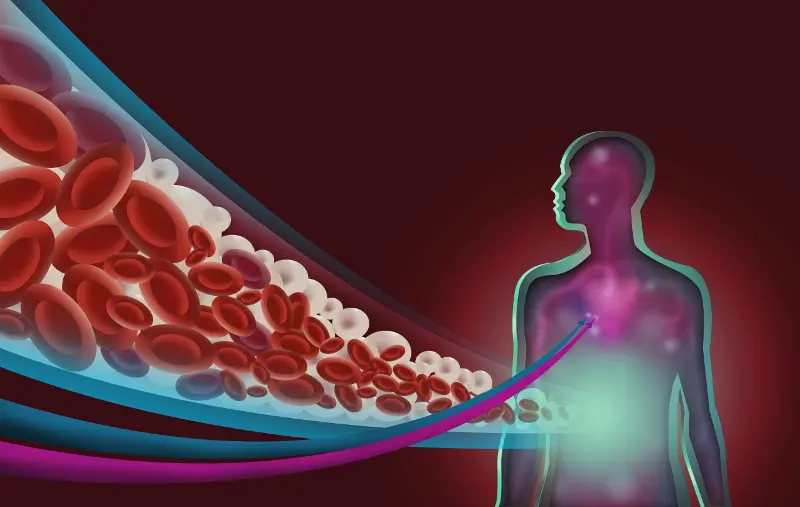

В кръвта липидите се транспортират с помощта на белтъчни молекули, като заедно с тях образуват комплекси, наречени липопротеини. Съществуват 4 основни вида липопротеини.KDL

Биологичната роля на липопротеините с ниска (т.нар. „лош“ холестерол – LDL) и висока плътност („добър“ холестерол – HDL) е свързана най-вече с пренасянето на холестерол. LDL пренася холестерол от черния дроб към тъканите и се счита за „опасен“, тъй като улеснява натрупването на холестеролови плаки по стените на кръвоносните съдове и е предпоставка за атеросклероза. Обратно, HDL извлича излишъците от холестерол от тъканите и стените на кръвоносните съдове и ги пренася до черния дроб, поради което се нарича „добър” холестерол.

Триглицеридите и холестеролът са видове липиди (мазнини), които циркулират в кръвта с различни функции.

Триглицеридите образуват енергия за човешкото тяло, използвайки излишните калории, а холестеролът се използва за изграждане на клетките и на някои хормони.